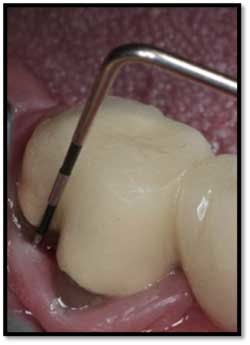

LL Quadrant#27M, now 2mm reduced from 6mm, tissue tight and firm

#26 DF, now 2mm from 8mm

#26 F now 2mm. All tissue is light pink, tight and firm.

Bone fill #26 and 27,no mobility